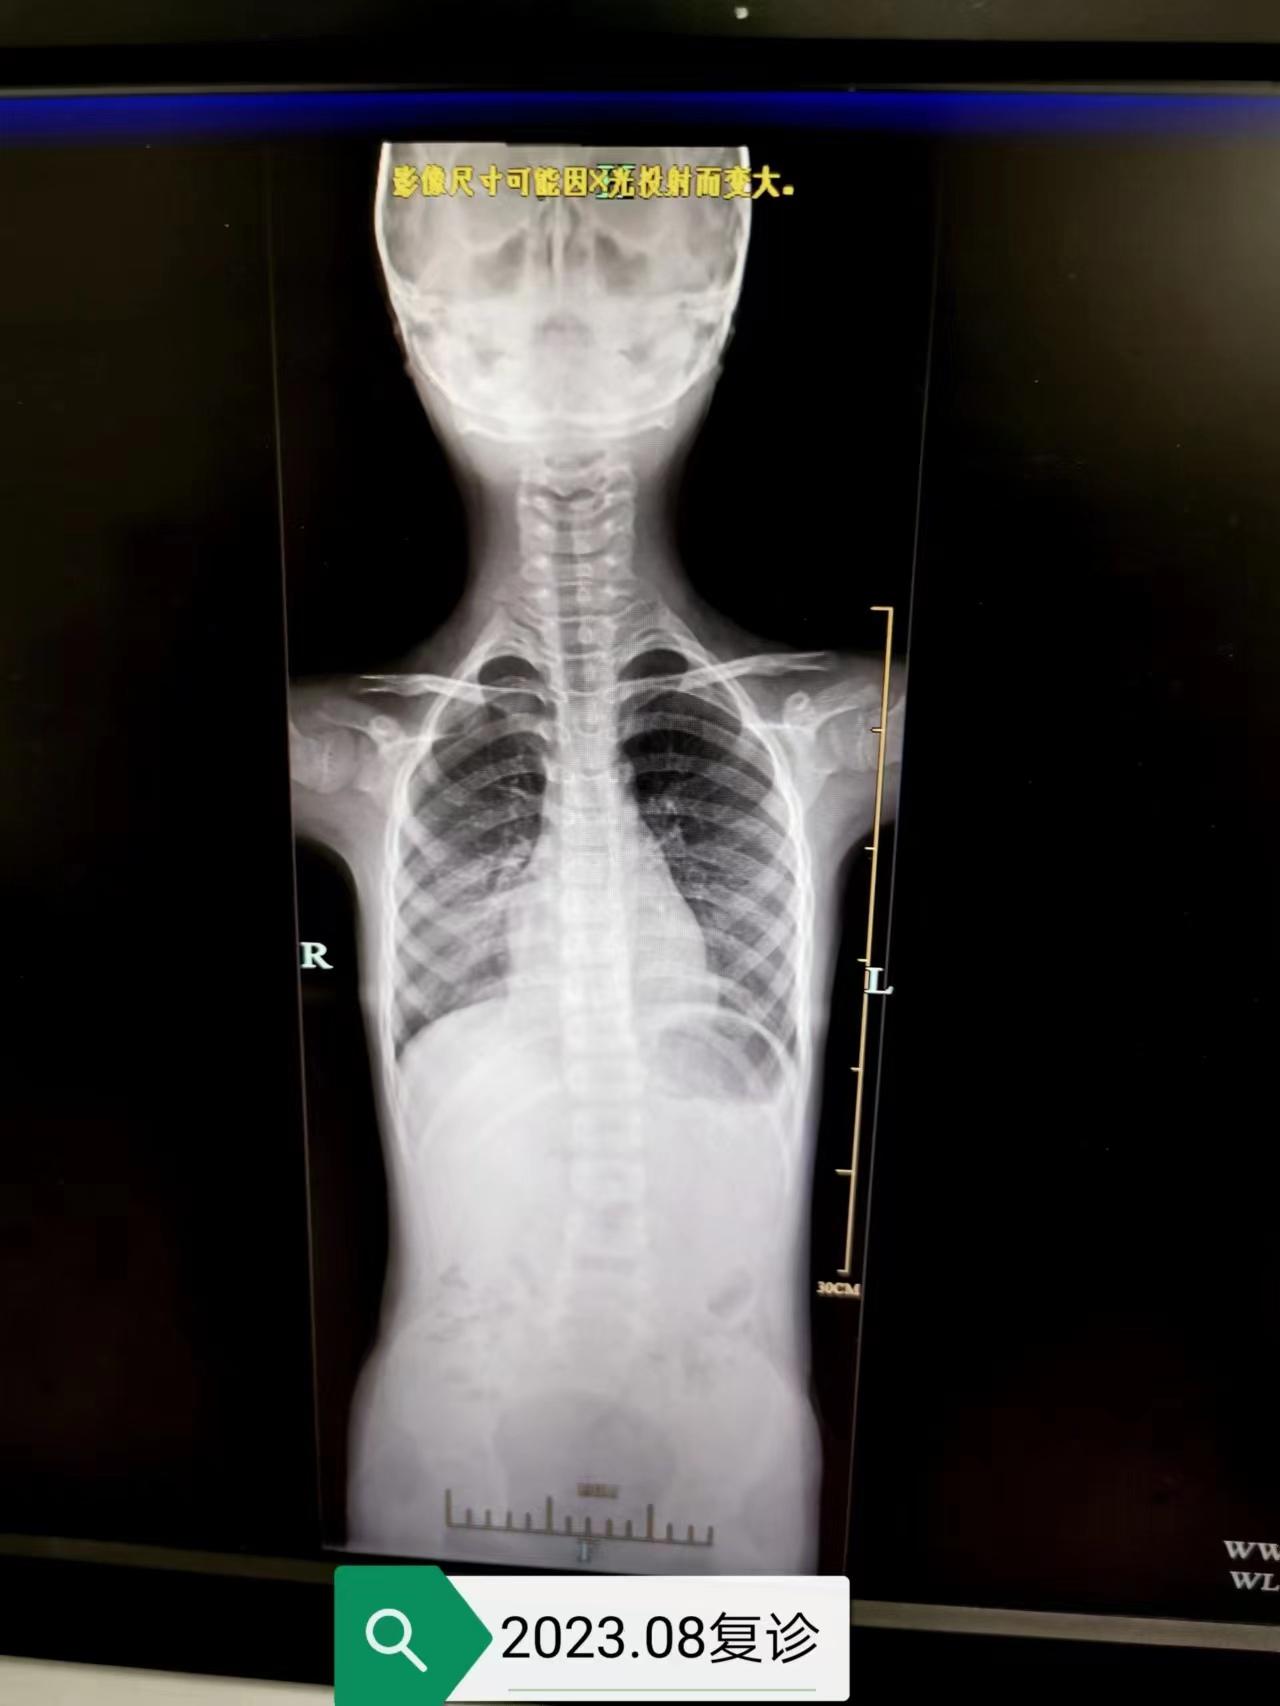

在康复运动医学科,有很多像小林一样每日坚持做矫正训练动作的孩子们,经过长期锻炼,孩子们在脊柱侧弯矫正与体态改善方面均取得显著的成果,让我们一起来看看效果吧!

矫正前VS 矫正后 矫正前VS矫正后 矫正前 VS矫正后